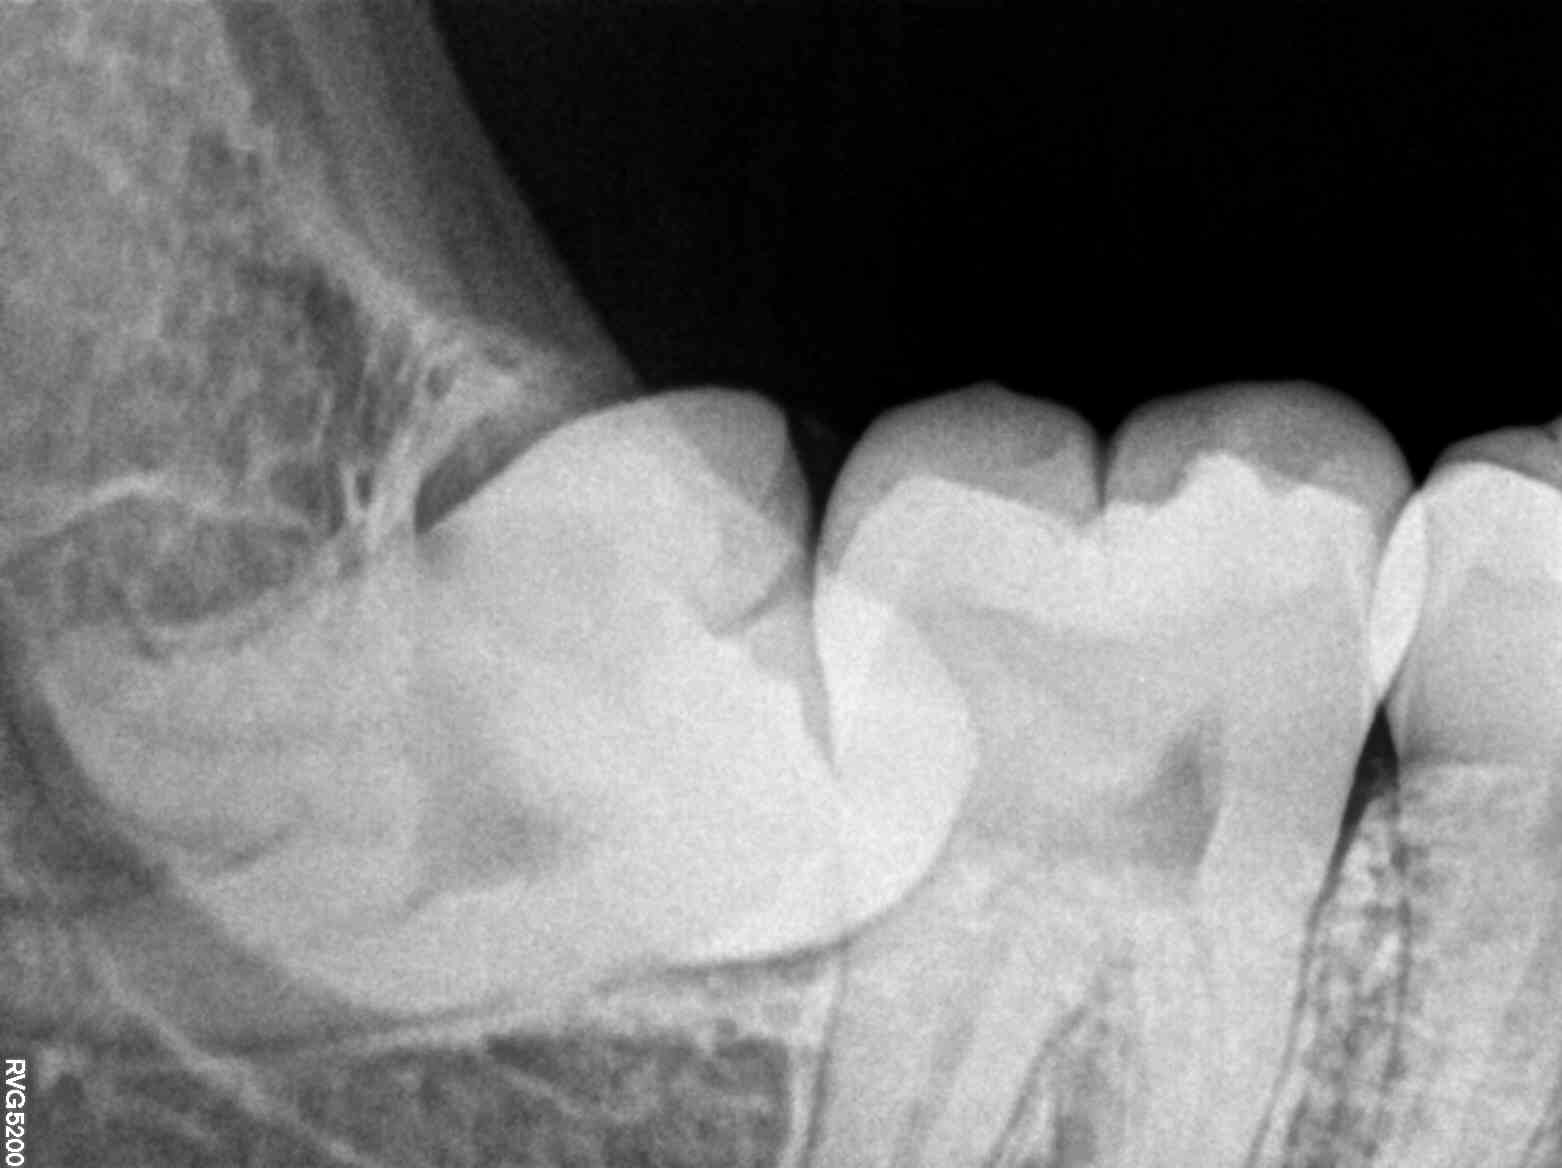

The solution came in the form of an advanced dental X-ray service. This state-of-the-art technology allowed the clinic’s team to delve deep into Ananya’s oral health, uncovering issues that were invisible to the naked eye. The detailed X-ray images revealed the root cause of her pain — an impacted wisdom tooth and an early-stage cavity.

For Ananya, this revelation was both a relief and a call to action. Finally, she had a clear understanding of her condition, which allowed her to move forward with a targeted treatment plan. The modern dental X-ray service had not only diagnosed her issues accurately but also provided her with peace of mind.